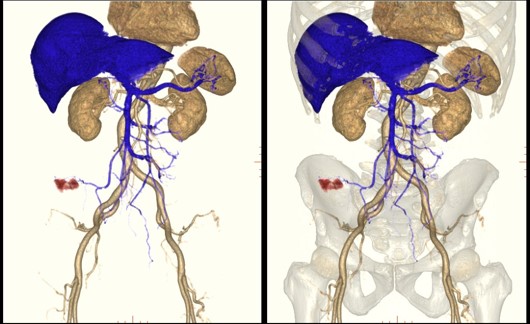

術前血管Map

16列では上記MPR同様、1.25㎜厚データから作成していたため、撮影断面に水平に走行する血管の描出能、撮影速度が遅いため肝臓上縁と大腸周辺で造影効果が異なり末梢血管の描出能に課題がありました。

また、FOVの中心から外れたエリアで画像劣化が顕著でした。 しかし、Maximaでは0.625㎜厚アキシャルデータからの再構成、撮影速度の向上、マルチフェイズのデータから造影効果が高い位相データで必要な情報を抽出し重ね合わせることができるため、体幹部の血管Map3D画像を精度よく作成できるようになり、安全なオペに寄与できるようになりました。